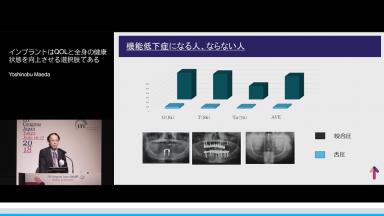

インプラントはQOLと全身の健康状態を向上させる選択肢である

高齢者の咬合力回復は,栄養摂取や全身の筋力維持に貢献できる.インプラント治療もQOL向上に大きく寄与できる可能性を有する.一方,術後の全身の健康状態の変化に対応したメンテナンスを術前から考える必要がある.